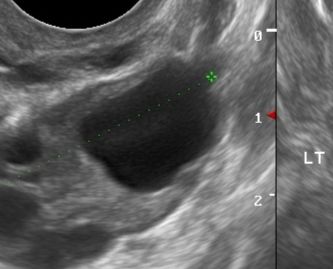

Ходила на УЗИ прям в день овули, жт не было, фоллик похож на амебу - только-только произошла. Сильно неровные края, не так как у вас. Вероятно, она произошла прямо после узи

У вас не могло быть ЖТ в момент приема, потому что ещё фолликул, который вот вот лопнет.